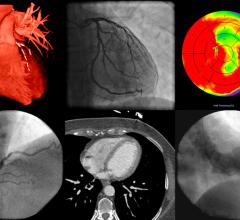

Radiology plays a crucial role in diagnosing — from guiding patients into the right treatment plans through follow-up ...